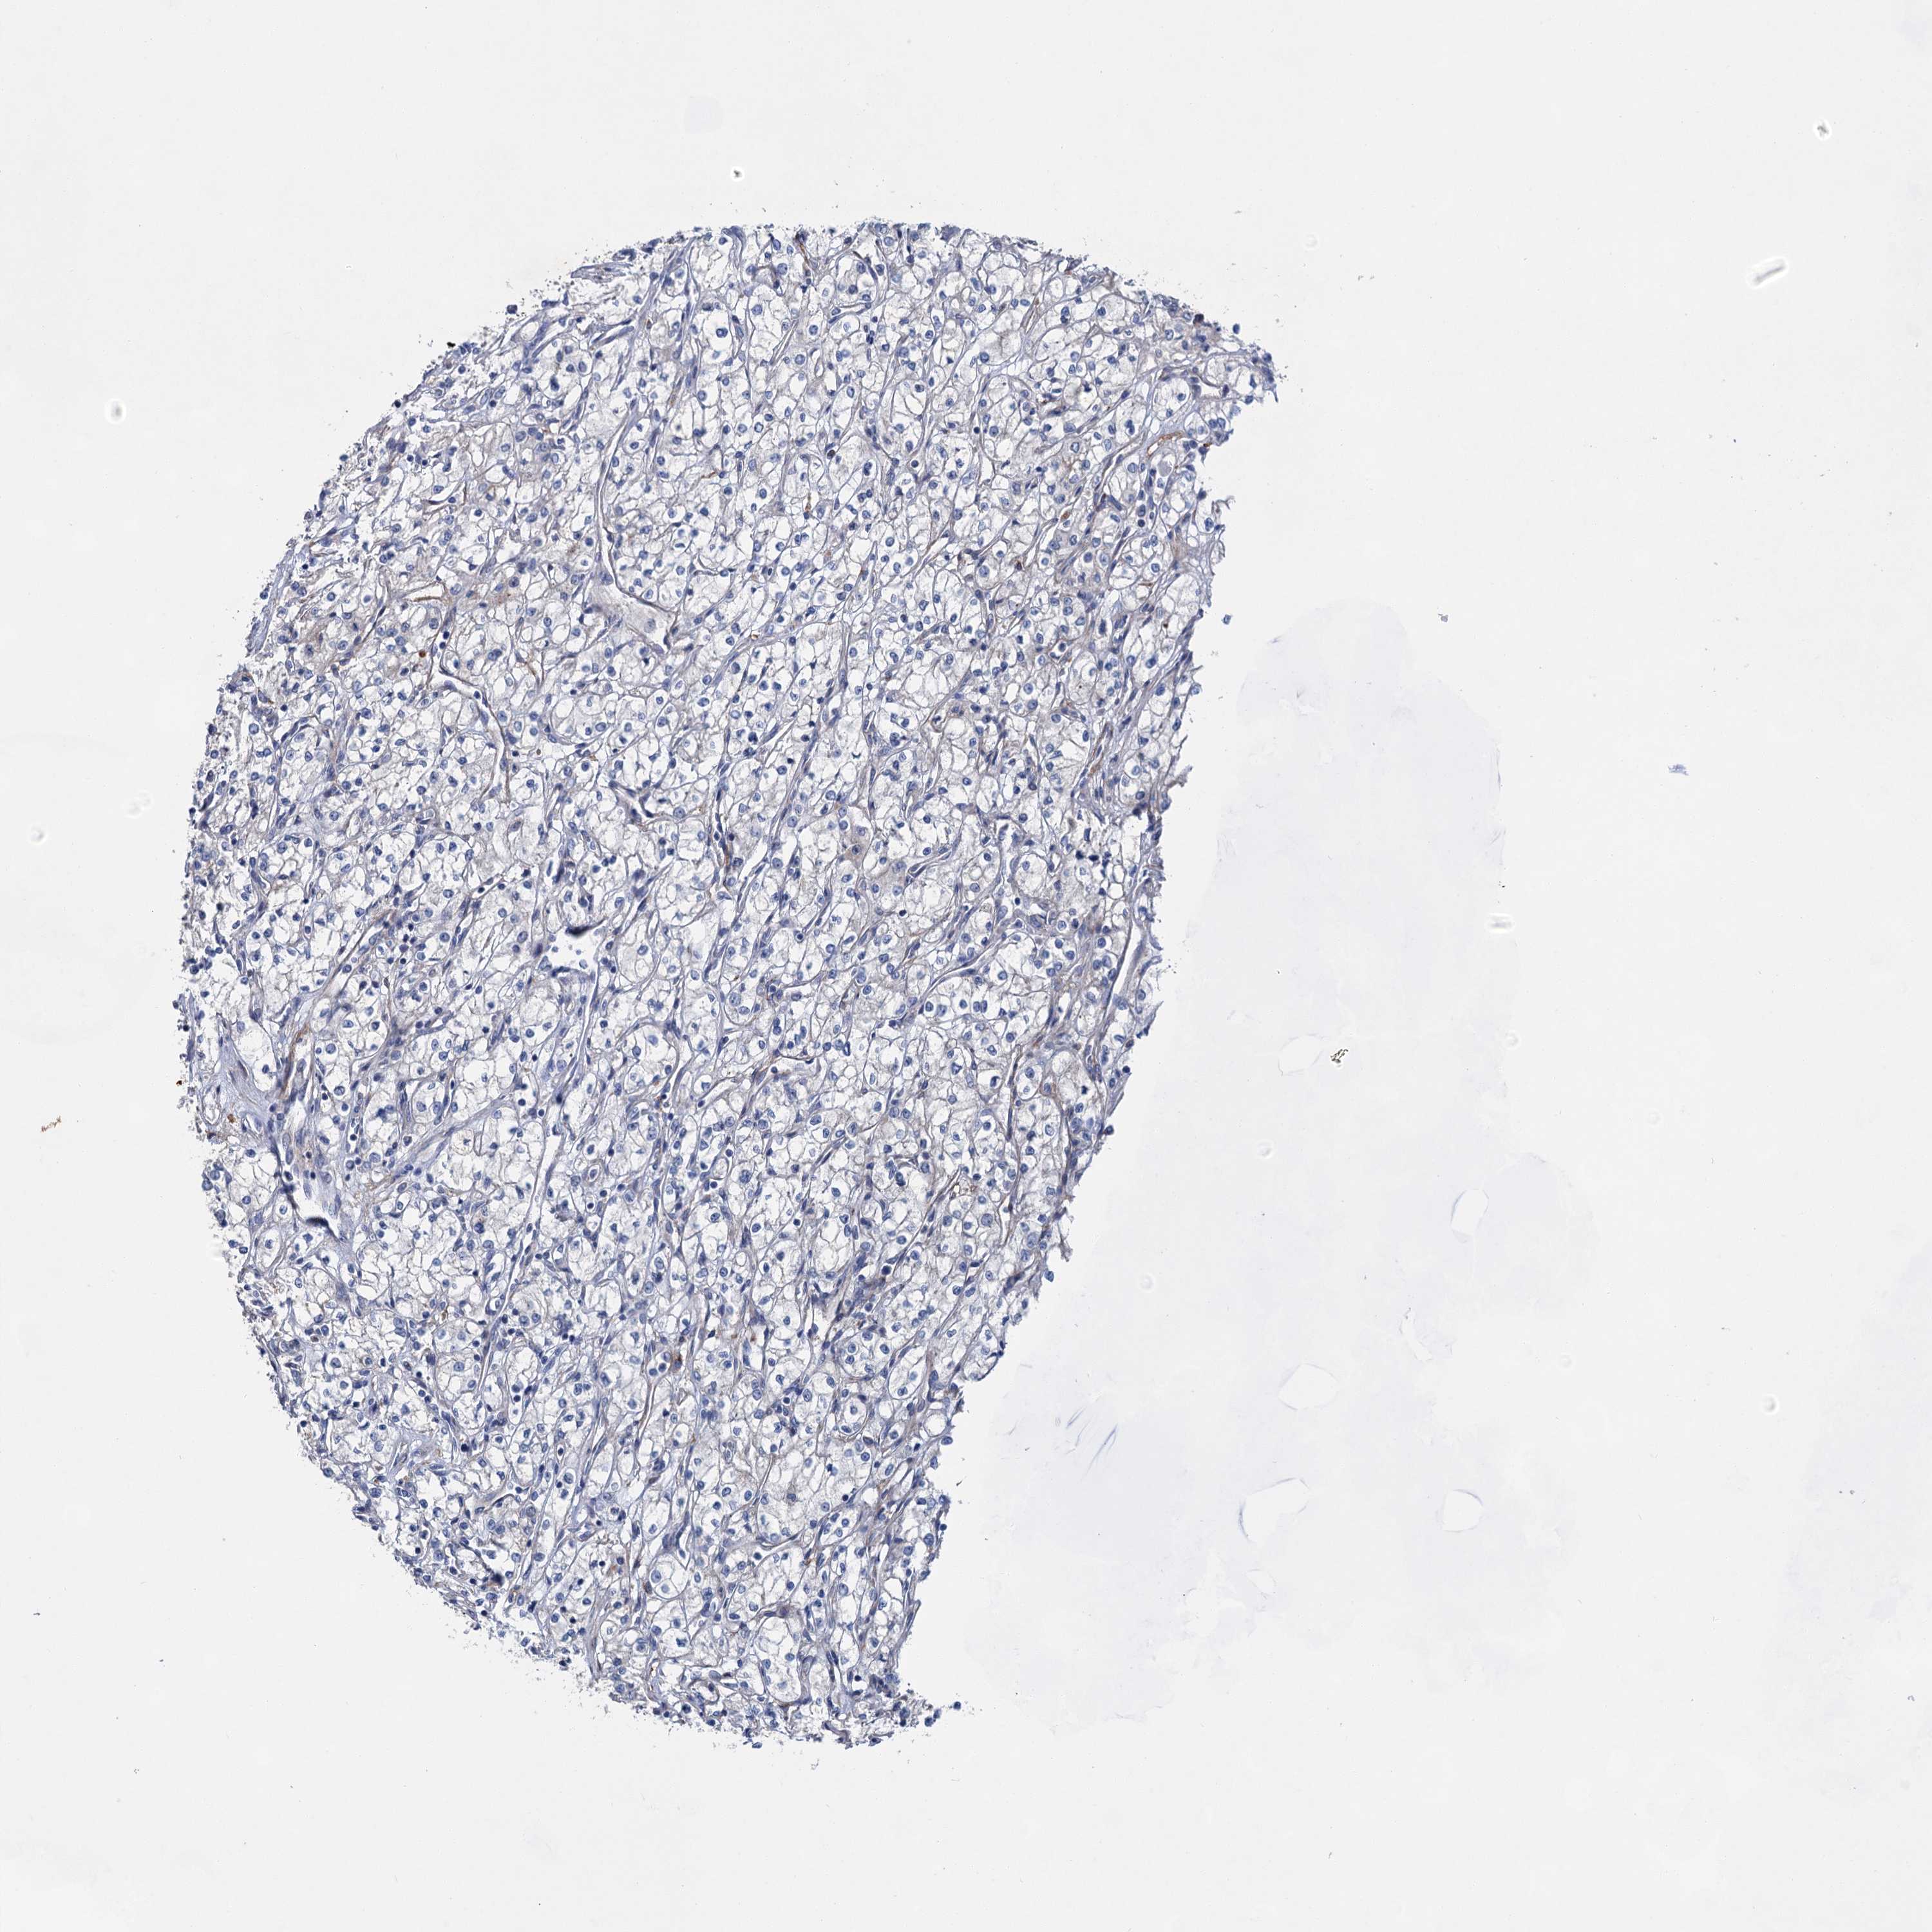

KIDNEY RENAL CLEAR CELL CARCINOMA (TCGA) - Interactive survival scatter ploti

GPR155 is not prognostic in Kidney Renal Clear Cell Carcinoma (TCGA)

Best expression cut offi

: 7.79

TCGA RNA samplesi

Average pTPM 5.1

Number of samples 521